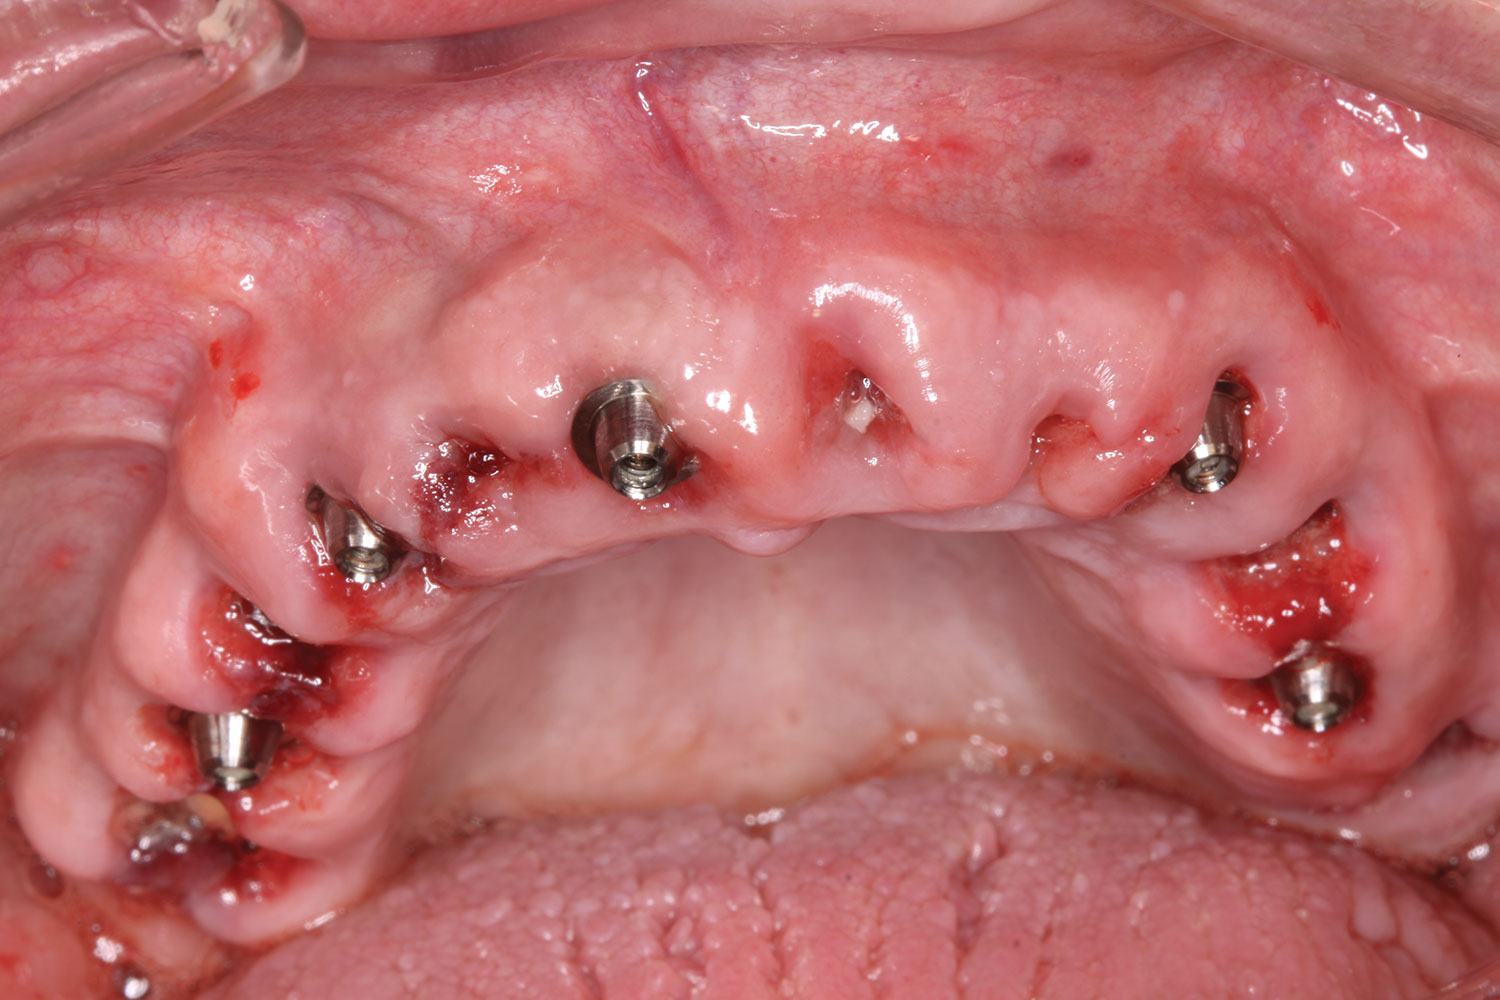

A week later the patient presented for surgery for extraction and replacement of her existing maxillary dentition with implants and a screw-retained provisional implant restoration. Teeth Nos. 2, 4, and 6 through 11, 13, and 14 were carefully extracted with attention paid to retaining site dimensions. Immediate implants were inserted into sites Nos. 4, 6, 8, 11, and 13 with high insertion torques in excess of

40 Ncm. Subsequently, multi-unit abutments were placed on all the implants and torqued to 30 Ncm, and scan gauges were placed on implant Nos. 8 and 11 (Figure 12 and Figure 13).

Fig 12. Partial extractions and placement of implants and multi-unit abutments.

Figure 12

Fig 13. Initial scan of scan gauges with residual teeth retained for reference.

Figure 13

Fig 14. All implants, multi-unit abutments, and scan gauges in place.

Figure 14

Fig 15. Completion of maxillary flapless immediate implant surgery and placement of multi-unit abutments.

Figure 15

Fig 29. Mandibular flapless immediate implant surgery completed and multi-unit abutments secured to implants.

Figure 29

Fig 30. All mandibular scan gauges in place.

Figure 30

Fig 33. Day of surgery; maxillary flapless immediate implant surgery completed and multi-unit abutments secured to the implants.

Figure 33